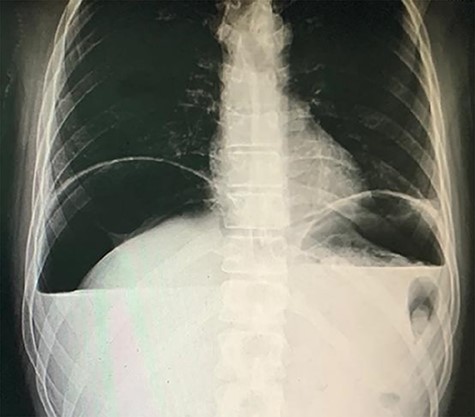

A 38-year-old male intravenous drug user presented to the emergency room with right iliac fossa pain of 3-hour duration. He had a previous surgical history of laparotomy and pan-proctocolectomy with ileoanal anastomosis indicated for his familial polyposis coli. Examination showed severe epigastric and right iliac fossa tenderness and rebound tenderness with a marked abdominal rigidity. Blood results showed blood urea nitrogen, 84; creatinine, 1.1; hematocrit, 63; K, 2.8; Na, 142; and total leukocytic count, 16.1. A chest X-ray was done and showed free air under the diaphragm (Fig. 1). An ultrasound showed a marked pelvic, peri splenic and perihepatic turbid collection.

After resuscitation with 2 liters of crystalloids in the form of 1-L 0.9% sodium chloride and 1-L Hartmann’s solution-Ringer acetate, the patient was transferred to the operation room, and a midline abdominal laparotomy was performed. After the evacuation of about 2 liters of collection from the abdominal cavity and peritoneal lavage done, a 2-cm ulcer defect appeared on the anterior aspect of the first part of duodenum (Fig. 2). There was no healthy omentum left from the previous operation to provide an adequate omental patch for repair. Therefore the falciform ligament was released and used as a patch for the ulcer that was fixed to cover the defect using interrupted Vicryl 2/0 sutures (Fig. 3). Methylene blue stain injection test was done through a nasogastric tube and no leakage was found. The postoperative course was uneventful, and contrast study was done on the seventh day postoperatively showing no contrast leakage and the patient was discharged.

2-cm ulcer appeared on the anterior aspect of the first part of the duodenum.